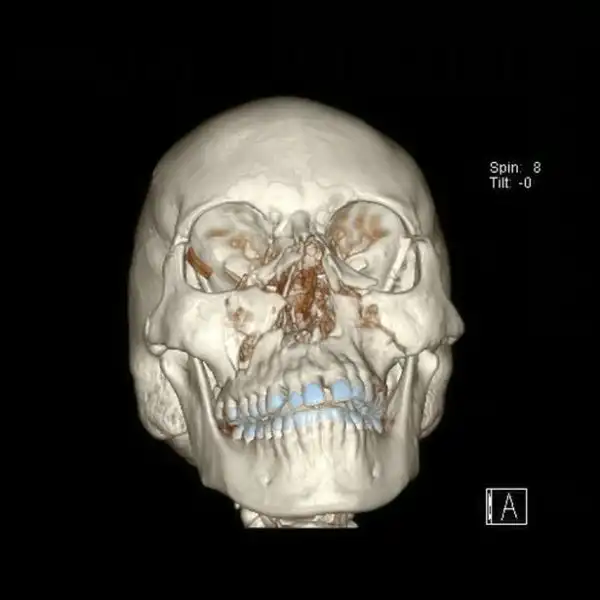

38-летняя педиатр Элизабет Калтон угодила под копыта испугавшейся лошади, в результате чего ее лицо превратилось в месиво. В ходе 10-часовой операции хирург восстановил череп пострадавшей, установив десяток металлических пластин и четыре десятка шурупов. Судя по снимкам Элизабет с врачом, результатом операции она довольна.